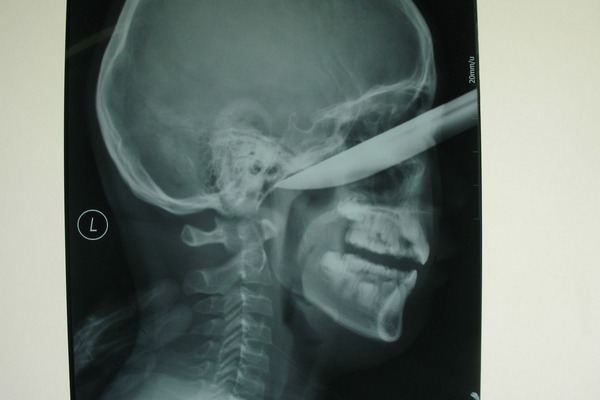

8②のハサミって医療ミスかよ。

リアルに本間先生みたいなミスする先生いるんだ…

最近のモータルコンバットで見たことあるような絵面

21はその後矢を引き抜いて飛び出た目玉を食べそう。

どこの世界に「弓」を飛ばして人に刺すバカがいるんだろうw

弓から矢を発射するんだろうがw